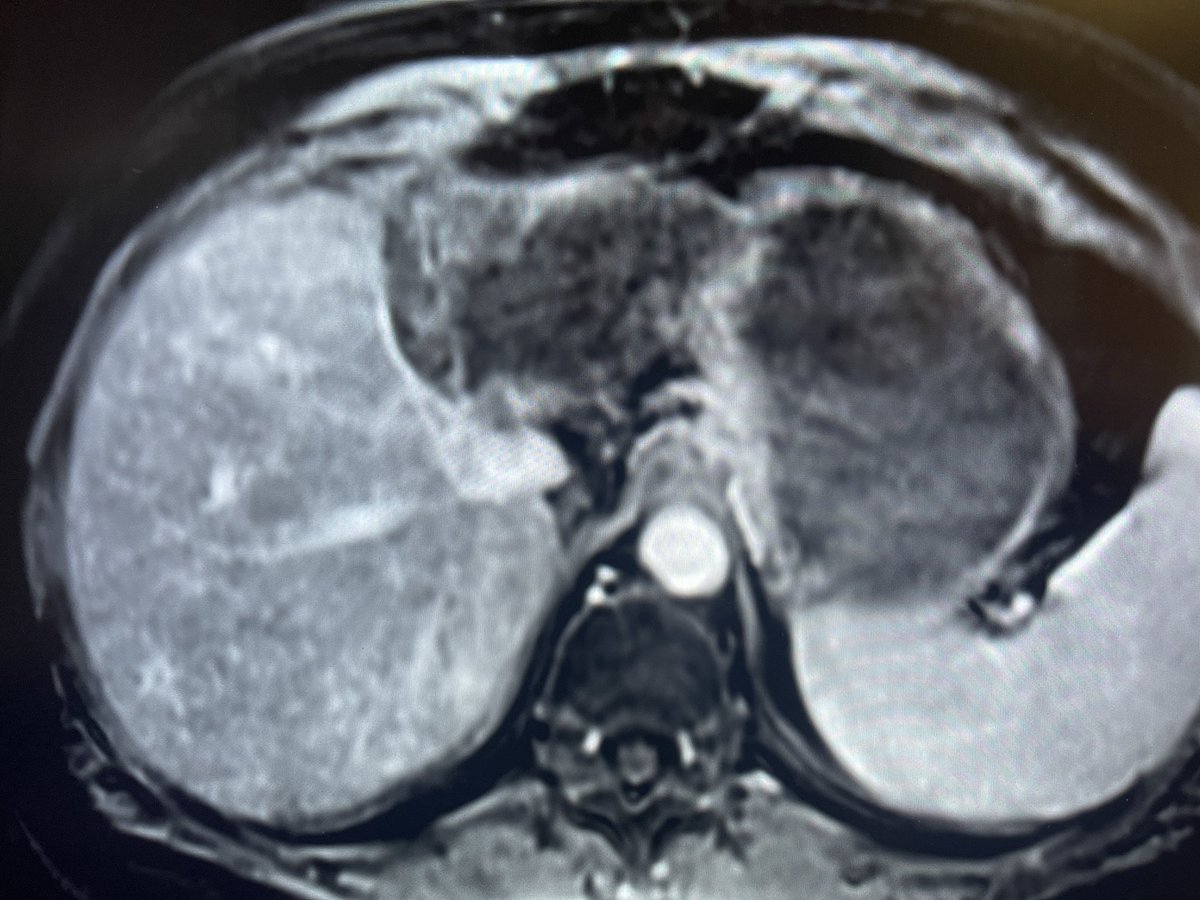

New study @AnnalsofIM bit.ly/2Km3KYu by @DrTalenfeld @WeillCornell: Percutaneous ablation for T1a #renalcancer has similar 5-year survival rates to radical nephrectomy but with far fewer 30-day complications and less #kidneyfailure.